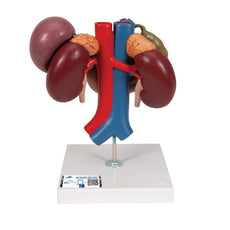

This Urinary System all-in-one-model shows:- Structures of retroperitoneal cavity

- Large and small pelvis with bones and muscles

- Inferior vena cava

- Aorta with its branches including iliacal vessels

- Upper urinary tract

- Rectum

- Kidney with adrenal gland.

One front half of a kidney is removable from the anatomical model of the urinary system. With easy to change male insert (bladder and prostate, front and rear half) and female insert (bladder, womb and ovaries, 2 lateral halves) the Urinary System model is a great teaching tool.

Dual Sex Urinary System model on baseboard.